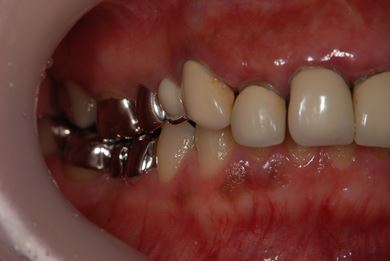

| 性別/年齢 | 女性 / 41歳 | ||||||||||||||||||||||||||||||||

| 主訴 | 歯が欠けたので、セラミック治療をお願いしたい。 | ||||||||||||||||||||||||||||||||

| 治療方針 | セラミック治療にて、審美的回復を行う。 | ||||||||||||||||||||||||||||||||

| 治療内容 | エンプレスオールセラミッククラウン4本(オールセラミック用土台4本) | ||||||||||||||||||||||||||||||||

| 総治療費 | 408,000円 | ||||||||||||||||||||||||||||||||

| 治療期間 | 4ヶ月 |